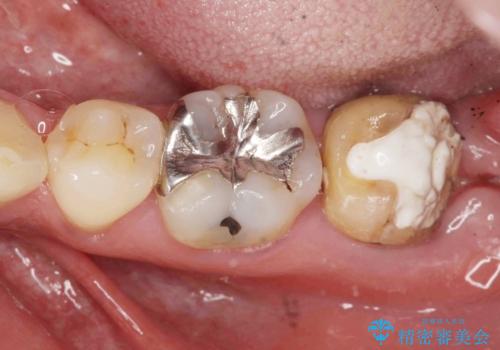

[ 金属アレルギー ] 銀歯を除去するメタルフリー治療

担当医 大元洋佑